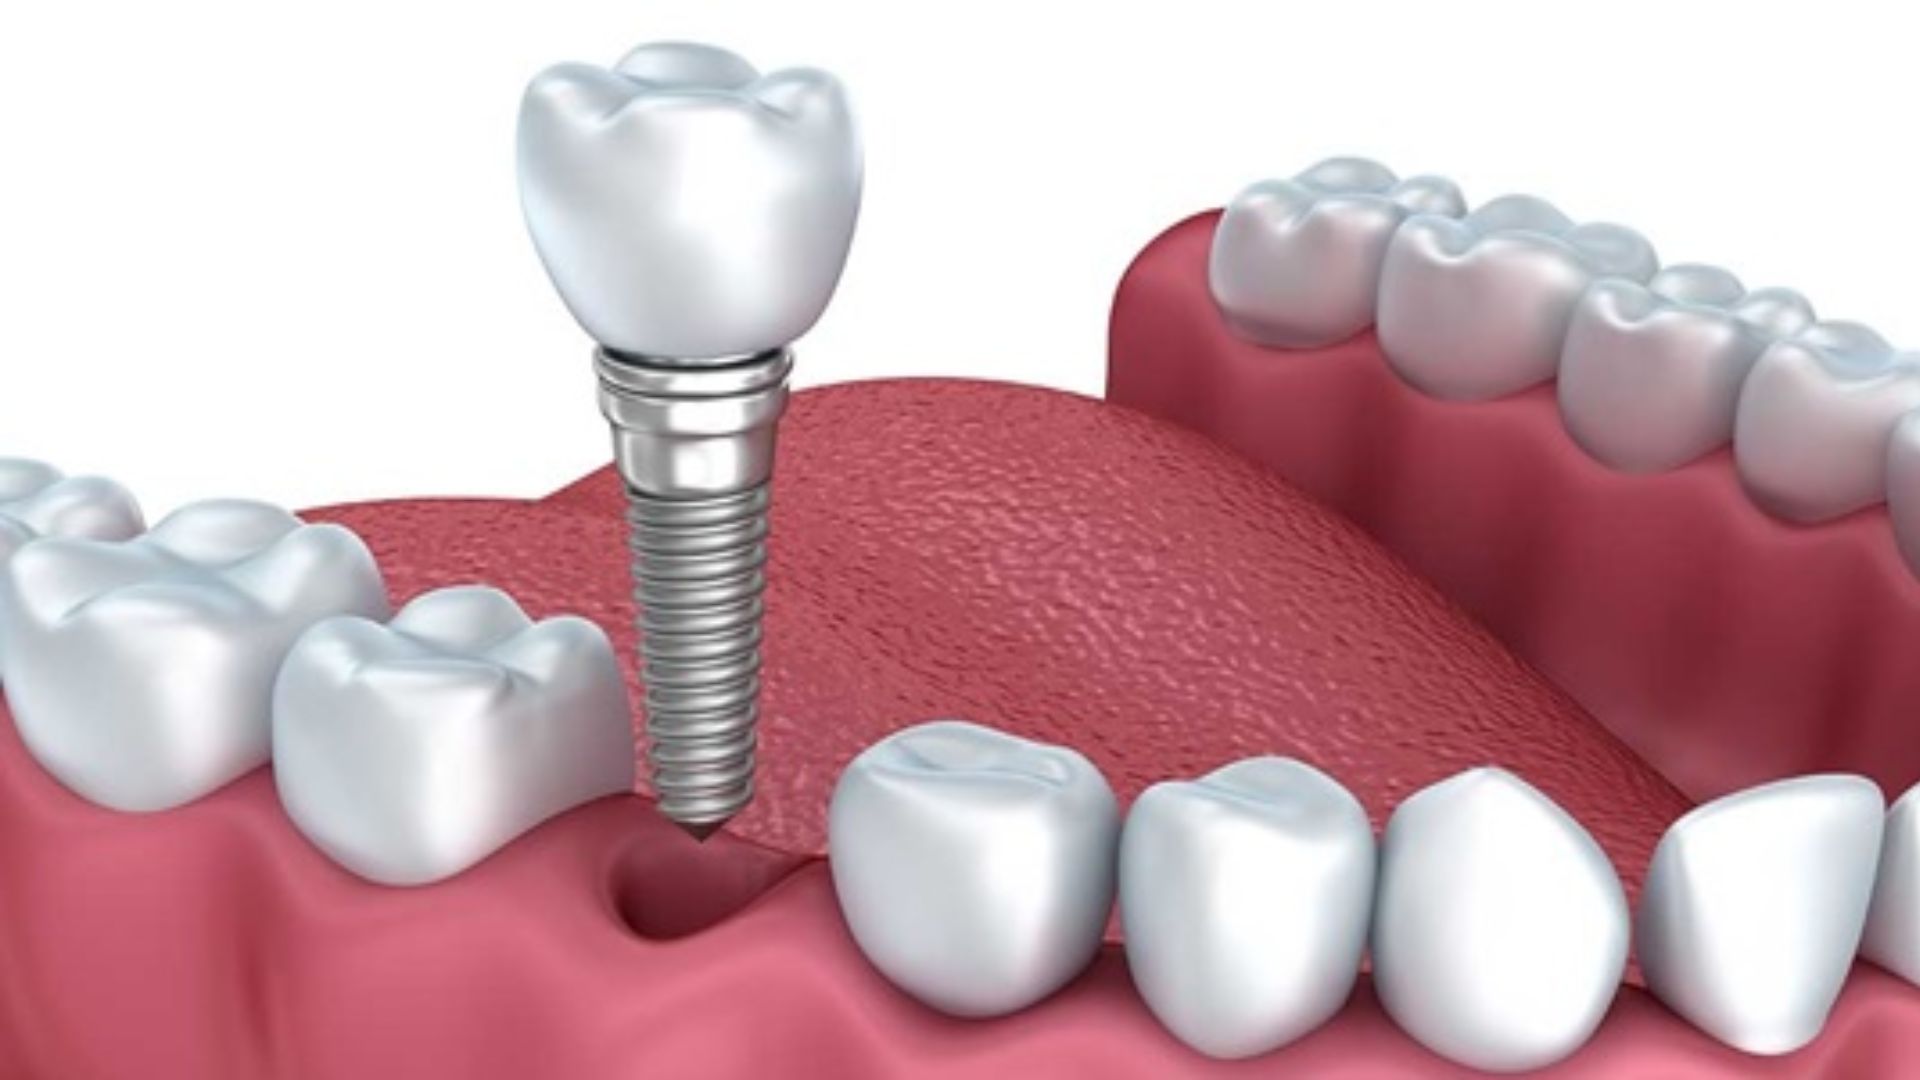

Trồng răng implant là một phương pháp thẩm mỹ răng được đánh giá tiên tiến nhất hiện nay, đang được nhiều người ưa chuộng và tin dùng bởi hiệu quả mà nó mang lại. Đâu là cơ sở trồng răng Implant Quận 1 uy tín? Giá cắm implant quận 1 tầm bao nhiêu? Cùng tìm hiểu thông qua bài viết dưới đây!

Tương tự như các phương pháp thẩm mỹ răng hay tái tạo răng khác, bạn cần nghiên cứu, tham khảo và xem xét những tiêu chí nào để lựa chọn nha khoa cấy răng Implant hiệu quả, chất lượng. Thông qua quá trình tìm hiểu, bạn có thể hạn chế rủi ro mắc phải khi gặp phòng khám nha khoa thiếu uy tín, tệ hại hơn chính là việc tiền mất tật mang. Cùng điểm qua một số tiêu chí “vàng” bạn nên chú tâm khi chọn lựa nha khoa trồng Implant.

Đến với Big Detal, bạn có thể yên tâm trao niềm tin, nhận giá trị với dịch vụ trồng răng impant tại đây. Một số trường hợp trồng răng implant tại Big Dental có thể kể đến như sau :

- Răng bị sâu, hỏng nặng cần phải nhổ bỏ

- Bẩm sinh bị mất 1 răng

- Có 1 hoặc nhiều răng khuyết thiếu trên hàm

- Răng hàm trên quá yếu dẫn đến không nâng đỡ được cầu răng

- Cả hàm răng cũ bị mất chức năng hoàn toàn dẫn đến cần phục hình răng mới

- Có răng giả lúc trước nhưng bị hỏng